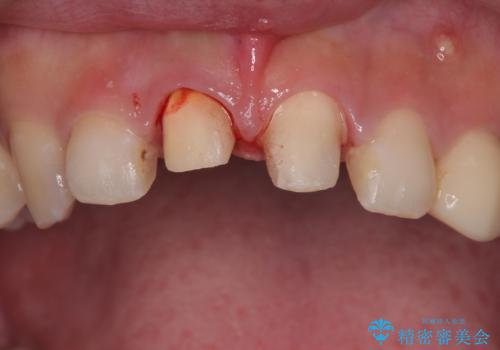

- 20代女性の患者様。

他院にて「上の前歯(右上中切歯)は抜歯してインプラントかブリッジにする必要がある」と診断され、大変ショックを受けられていました。

すでに根管治療を受けた歯でしたが、急に担当医が変わり、「抜歯が必要」とだけ説明されたことに不安感を抱き、当院を受診されました。

左上中切歯と犬歯も仮歯のままで、将来への不安が大きかったご様子です。

抜歯を避けられない場合でも、「即日でインプラント治療+仮歯装着」により見た目を損なわないで治療を終えることができました。

抜歯をしてインプラントを埋入してから、4か月で最終補綴物(オールセラミッククラウン)の装着まで終えることができ非常に満足いただきました。